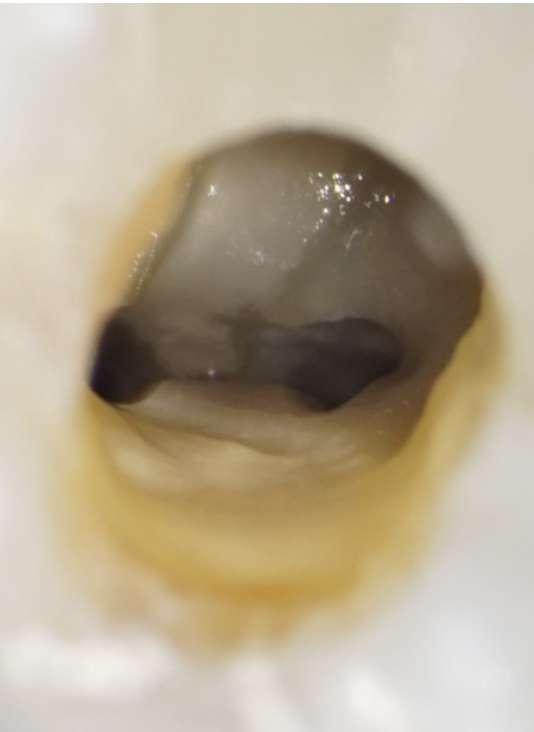

Die Revisionsbehandlung erfolgte in zwei Sitzungen. Nach Anlegen des Kofferdams wurde die provisorische Füllung entfernt und die Zugangskavität gereinigt. Im Anschluss erfolgte die intrakoronale Diagnostik (Abbildung 11). Es zeigte sich bakteriell besiedeltes Wurzelfüllmaterial im mesiobukkalen, distobukkalen und palatinalen Kanal. Das Orifizium des mesiobukkalen Kanals war in palatinaler Richtung erweitert. Die Entfernung eines mesialen Dentinüberhangs mit langschaftigen Rosenbohrern legte das weit nach palatinal verlagerte Orifizium des zweiten mesiobukkalen Kanals frei. Die Entfernung des Wurzelfüllmaterials erfolgte mithilfe von EdgeFile X7 der Größe 25.06, und 17.06 in Crown Down Technik um die Verschleppung von Keimen und bakteriell besiedeltem Wurzelfüllmaterial nach apikal zu reduzieren. Die Erschließung und initiale Aufbereitung des zweiten mesiobukkalen Kanals wurde mithilfe der EdgeFile X7 der Größe 17.04, 17.06 in alternierender Weise wie oben beschrieben durchgeführt. Nach elektrometrischer Bestimmung der Arbeitslänge aller Kanäle wurde die Präparation mit EdgeFile X7 auf voller Arbeitslänge fortgesetzt. Im ersten mesiobukkalen Kanal, distobukkal und palatinal wurde die Aufbereitung mit EdgeFile X7 der Größe 40.06 abgeschlossen, während der zweite mesiobukkal Kanal bis 30.06 aufbereitet wurde (Abbildung 13).

Abbildung 11: Nach Ausarbeiten der primären Zugangskavität; Darstellung des mb2 in der Nähe des palatinalen Kanals